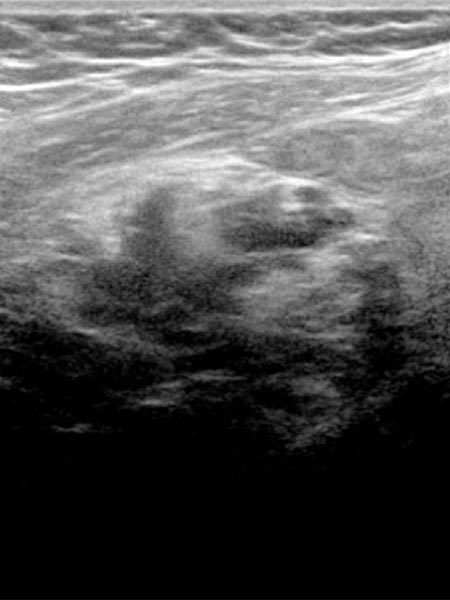

Bildgebung vor der Schwangerschaft im Ultraschall mit 10,4 MHz Linearschallkopf. Nachweis einer intramuskulären subfaszialen venösen Malformation mit multiplen echoverminderten Venenkonvoluten.

In der 21. Schwangerschaftswoche dann deutliche Vergrößerung der venösen Malformation im Ultraschall mit 10,4 MHz Linearschallkopf. Progredienz der intramuskulären subfaszialen venösen Malformation mit multiplen echoverminderten Venenkonvoluten und deutlicher Strukturauflockerung der echoverminderten und nun zum Teil auch echovermehrten Venenkonvolute durch Gerinselbildung.